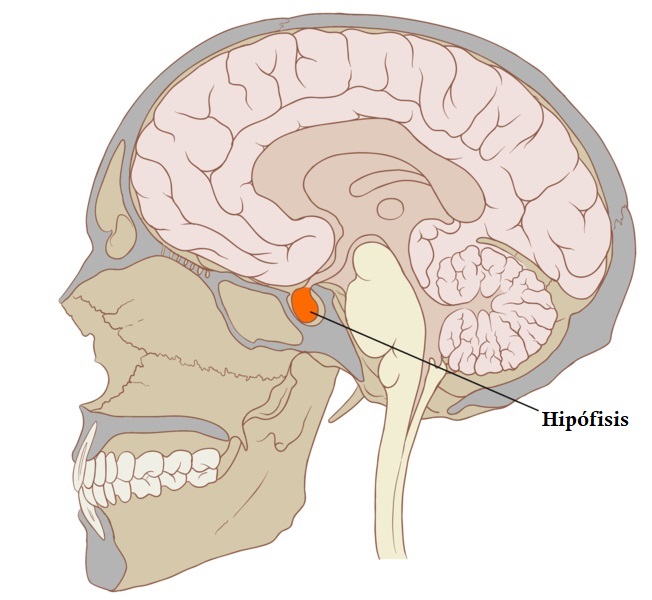

Se trata de una glándula compleja ubicada en un espacio óseo conocido como silla turca del hueso efenoides. Este espacio está situado en la base del cráneo, concretamente en la fosa cerebral medial, la cual conecta el hipotálamo con el tallo pituitario o tallo hipofisario.

Localización

La hipófisis es una glándula compleja que se aloja en un espacio óseo que se llama silla turca del hueso esfenoides. Esta región está situada en la base del cráneo, ocupando una zona conocida como fosa cerebral media.

La fosa cerebral media es la región del organismo que conecta el hipotálamo con el tallo pituitario. Posee una forma ovalada, y un diámetro antero-posterior de 8 milímetros, transversal de 12 milímetros y vertical de 6 milímetros.